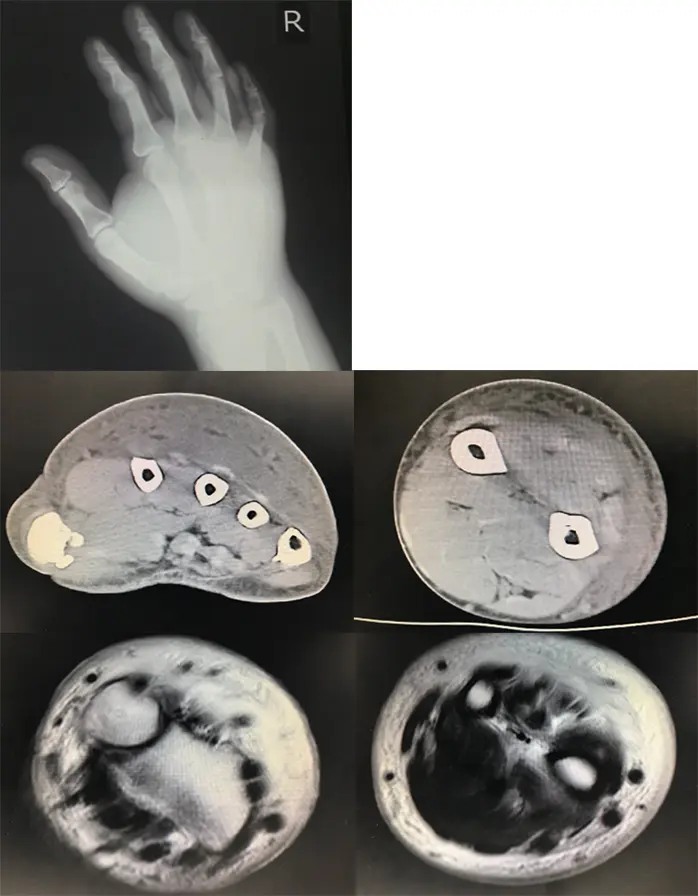

画像所見

単純X線像にて軟部組織陰影の増強を認め、CTおよびMRIにて、手背から前腕にかけて筋膜に沿った膿瘍形成を認めた。